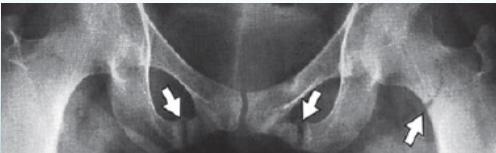

Characteristic Sign: Looser’s Zones

- Poorly healing stress fractures typically occurring at:

- Neck of scapula

- Neck of femur

- Pubic bones

Looser’s zones Z are short lucent bands running through the cortex at right angles, usually going only part way across the bone